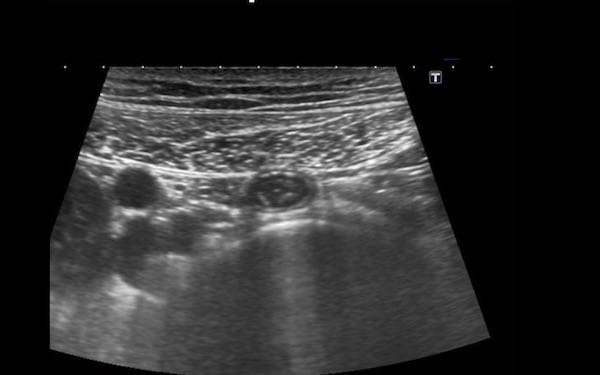

Ruột thừa bình thường (đầu mũi tên) được phân biệt với ruột non dựa vào vị trí, kích thước, sự vắng mặt của nhu động ruột, sự gắn kết với cực manh tràng (c.p.) và đầu tận cùng bịt kín (mũi tên).

Đầu mù của ruột thừa bình thường được thể hiện rõ ràng bằng cách sử dụng “kẹp mini”.